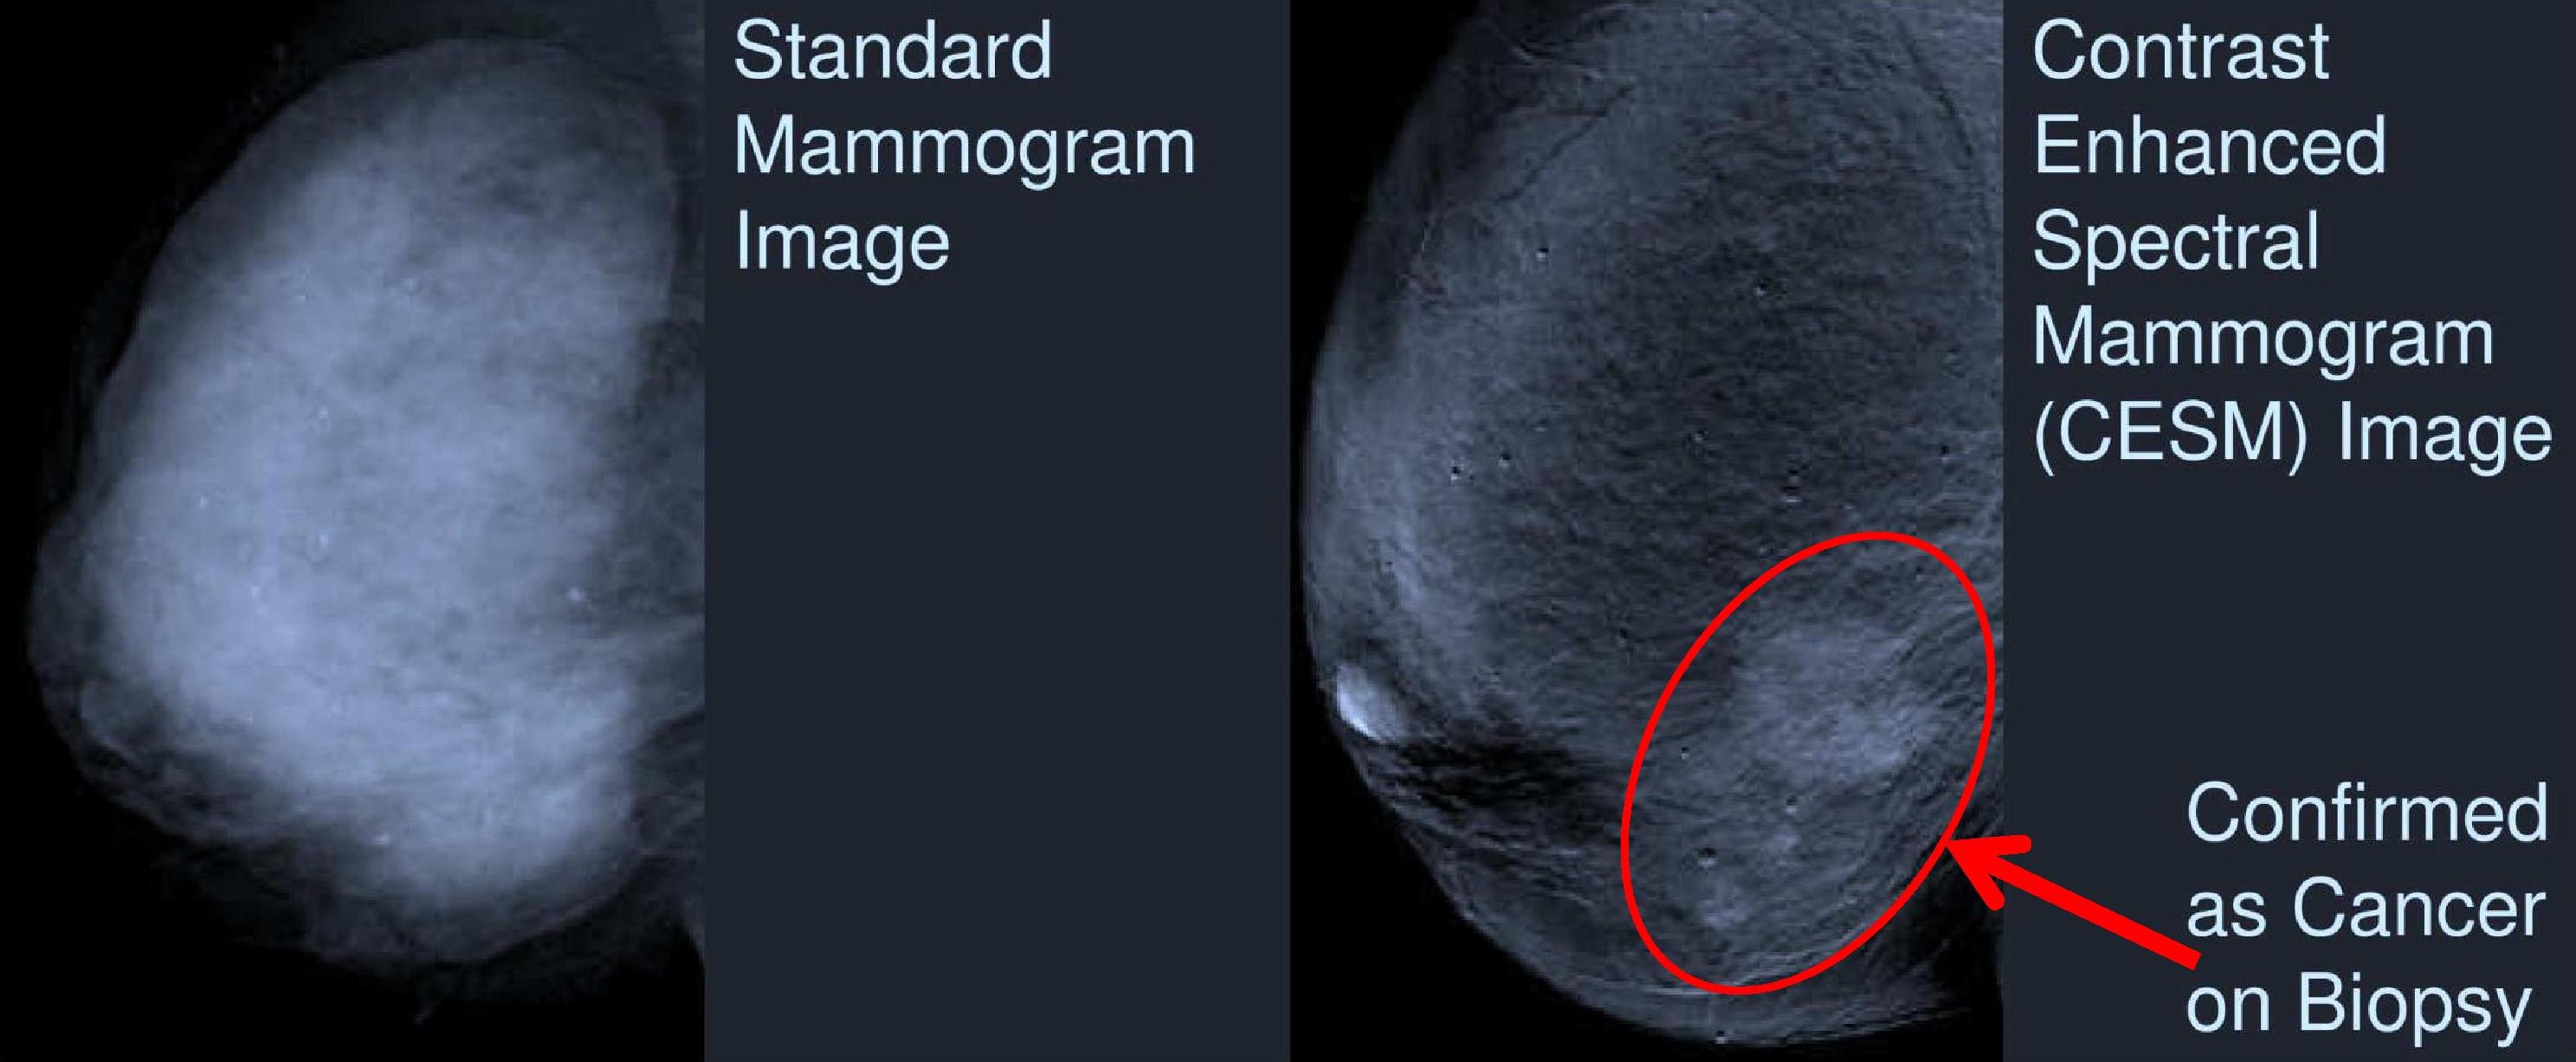

OXNARD, Calif., July 24, 2012 (GLOBE NEWSWIRE) -- Rolling Oaks Radiology, a division of RadNet, Inc. (Nasdaq:RDNT), a national market leader providing high-quality, cost-effective diagnostic imaging...